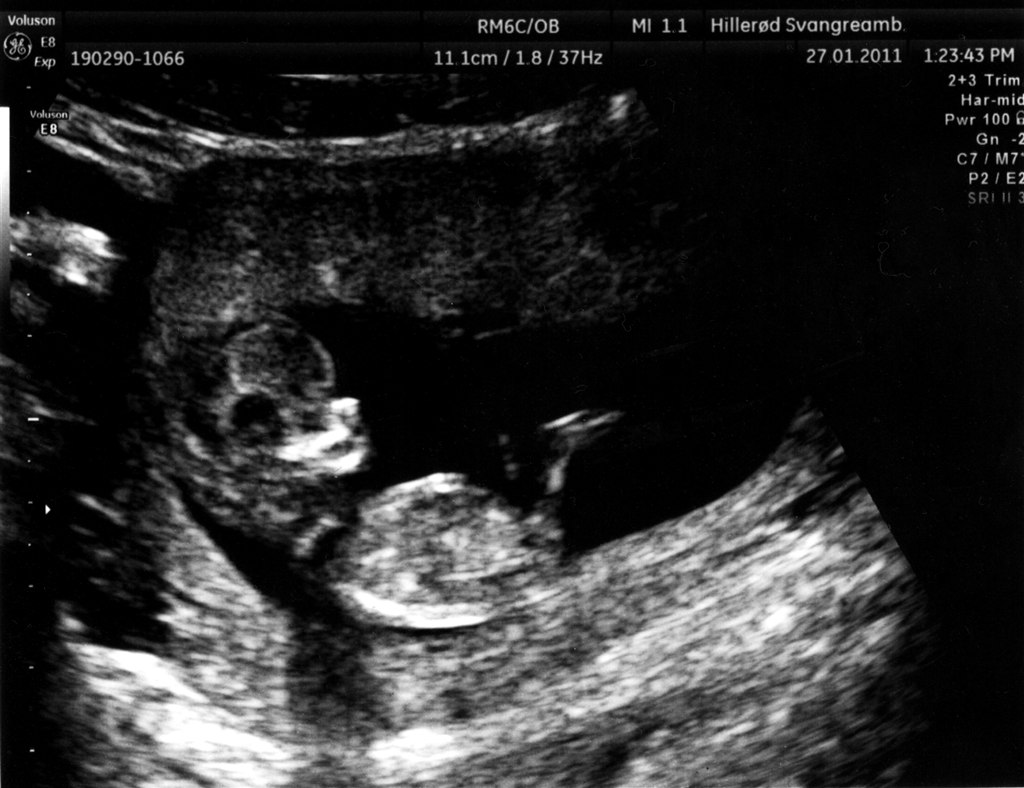

.. Så fik mig og min søde kæreste endelig set det lille liv!

Så fantastisk - intet mindre !

Alt var som det skulle være, og vi har et sundt og rask lille ven, liggende i sin lille hule.

Vedhæftede fotos (klik for at se i fuld størrelse)